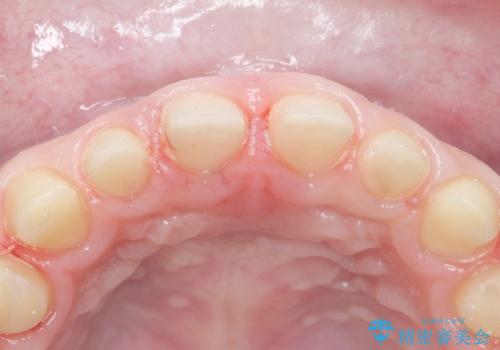

- K-POP(Kポップ)アイドルのような歯にしたいと希望され来院された患者様です。

矯正を途中でやめてしまったとのことで、歯に矯正の接着材が残っており着色も顕著でした。

奥歯の咬合面にはレジンが盛られた状態でした。

見た目と咬み合わせを改善するため、セラミッククラウンによる治療を行いました。